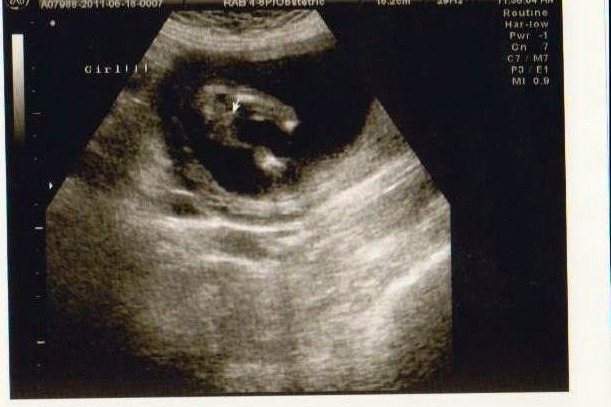

15 week 1 day...girl???

Hey ladies!!!! I had an elective gender scan yesterday, dating at 15 weeks and 1 day, tech said she was 100% certain this was a girl, but she gave me a not so good image to confirm... does everyone / anyone see the infamous 3 lines?? we have 2 boys now, and at our last little guys 15 week scan you could clearly see his goodies, where there was nooooo goodies at all.... really hope she was right!!! :DD::nails::ttcgirl::omg:

Yep a girl alright!!! Congrats!!

i never saw my dd3's 3 lines at 19 weeks but the sonographer did, they know what to look for,im sure it'll be a girl!